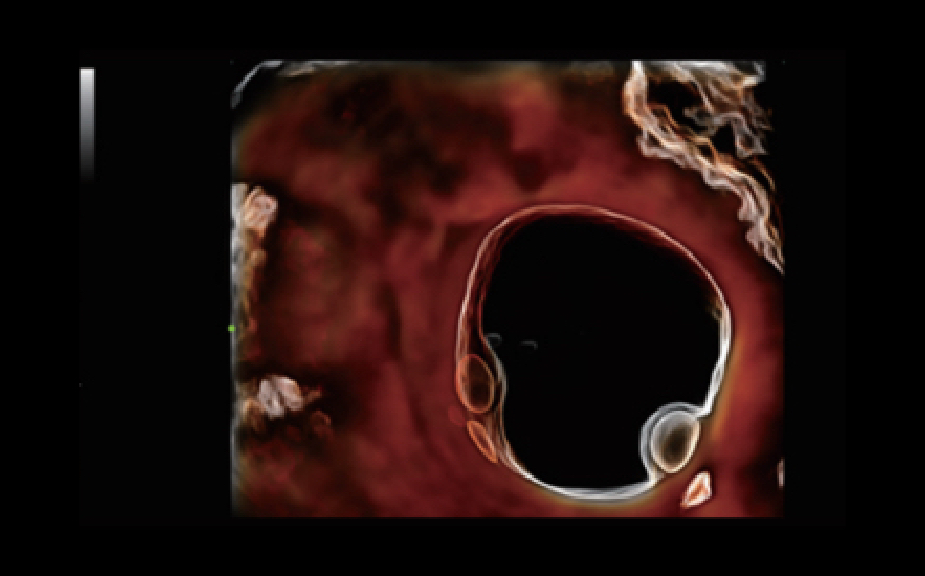

De Nuewa I9, speciaal ontworpen voor vrouwen en neonatale gezondheidszorg, biedt een innovatieve ervaring van binnenuit. Deze innovaties zijn ontwikkeld op basis van diepgaande inzichten in complexe klinische scenario's en bieden nauwkeurige en tijdige antwoorden, evenals een uitstekende effici?ntie en opmerkelijke gebruikerservaring.

Het ZST+ platform is een buitengewone innovatie en revolutie in de wereld van ultrasound. Het transformeert ultrasoundgegevens van conventionele bundelvorming naar kanaalgegevensverwerking. Het overwint de traditionele afweging tussen ruimtelijke resolutie, temporele resolutie en weefseluniformiteit, en levert een uitzonderlijke beeldkwaliteit voor oneindige beeldvormingsoplossingen met non-stop verbeteringen.